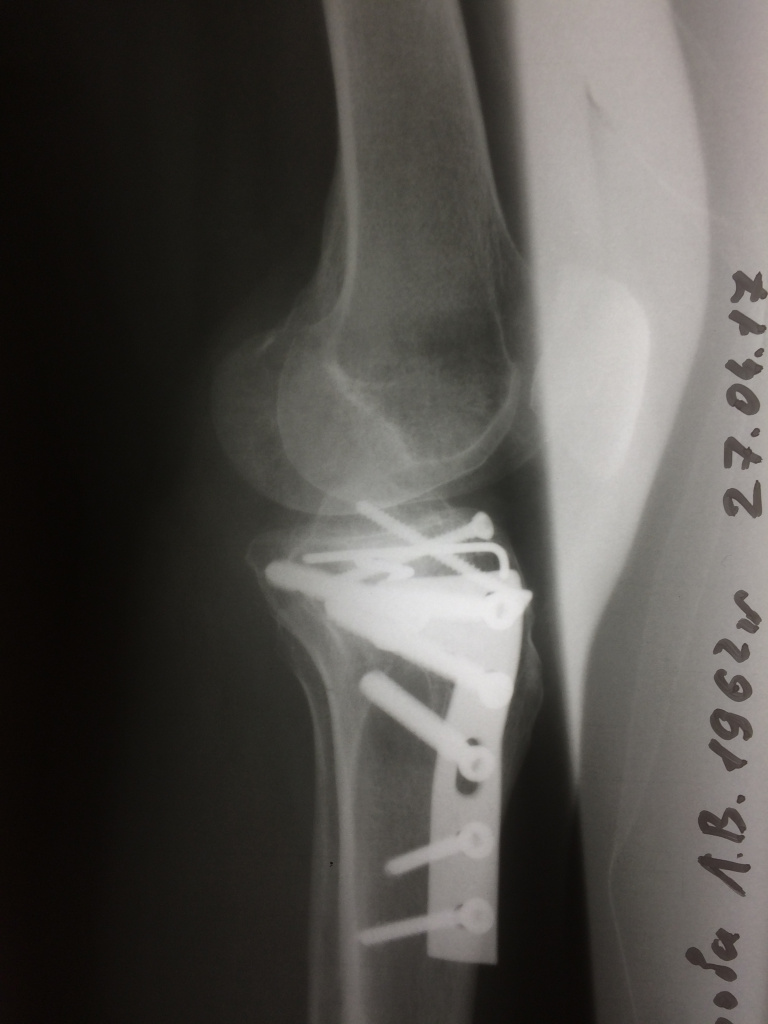

Использование материала Остеоматрикс при импрессионном оскольчатом переломе наружного мыщелка большеберцовой кости по типу Schatzker II

Использование материала Остеоматрикс при импрессионном оскольчатом переломе наружного мыщелка большеберцовой кости по типу Schatzker II.

Операция - открытая репозиция, остеосинтез большеберцовой кости опорной пластиной с костной ксенопластикой маетриалом "Остеоматрикс". На контрольных снимках в три и шесть месяцев имеется консолидация перелома, миграции фиксатора нет, имеется остеоинтеграция ксенопластического материала. Функция коленного сустава полная.